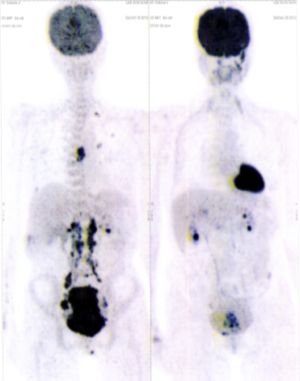

CASE NO: 2 (HEPATOCELLULAR CARCINOMA)

A 40+ man with hepatocellular carcinoma, an incurable cancer. After 2 treatment, the activity of the hepatocellular carcinoma is less.

CASE NO: 2 (HEPATOCELLULAR CARCINOMA) - After a few more treatments

After another few treatment, the activity of the hepatocellular carcinoma is much less. The patient never came back for further treatment, but this case, and case no: 1, shows that incurable hepatocellular carcinoma, often seen in hepatitis B and C patients, can be cured.